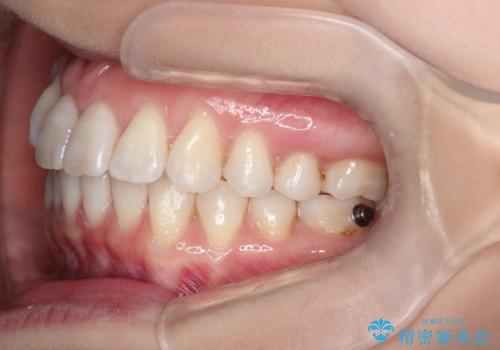

- 上の前歯のねじれを気にされて来院されました。

右上の前から2番目の歯が90度近くねじれて並んでいました。

こちらを当初セラミックでの治療をご希望でしたが、セラミック治療の限界と矯正治療のメリットをご説明をさせていただきました。

患者様に考えていただき、矯正治療で前歯をきれいにすることとしました。

インビザラインを使用して矯正することとしました。